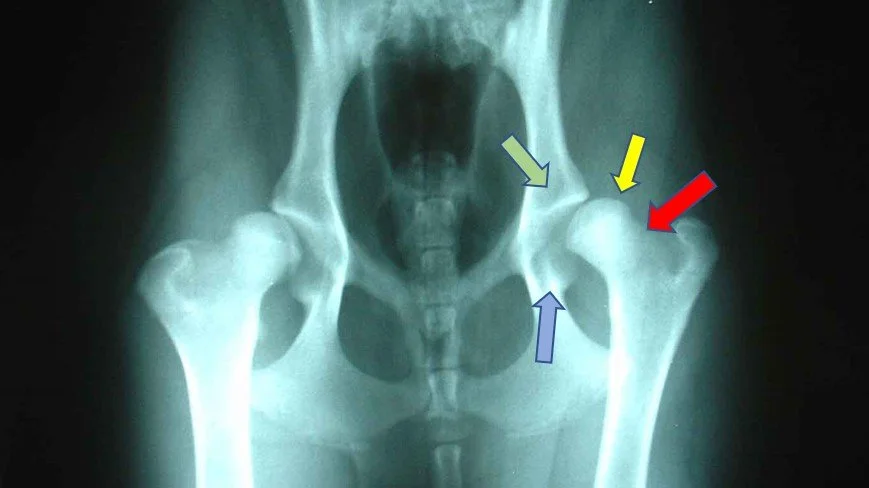

X-rays under an anaesthetic is essential. This allows us to manipulate the joints without causing any pain to our pets and thus get a really good image of the joint. There are several areas we examine on the X-ray shown in the picture.

• Yellow Arrow – the location of the “ball” of the joint should be inside the socket

• Red Arrow – new bone growth can occur, known as osteophytes – this is a sign of osteoarthritis being established

• Blue Arrow – a denser back part of the socket joint is another sign of advanced disease

• Green Arrow – the bright white line occurs when more bone is being added to strengthen the joint – this is known as sclerosis.